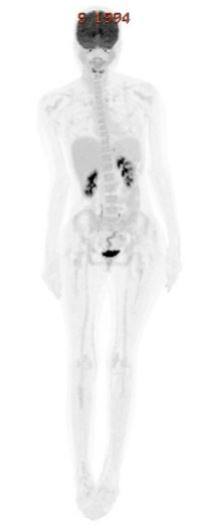

Imaging with PET-CT showed multiple FDG-avid supra- and infra-diaphragmatic lymph nodes (SUVmax 14.4) and mild splenomegaly (Figure 2). Biopsy of a right cervical lymph node confirmed T/myeloid sarcoma, with blasts positive for MPO, CD3, CD7, BCL2, and CD99, variably expressing CD5, CD117, and CD34, with focal TdT positivity and a Ki-67 index exceeding 90%. Given the high disease burden, debulking with flat-dose cytarabine (1 gram) was administered, followed by induction therapy using CALGB 10403, a pediatric-inspired ALL protocol (vincristine, daunorubicin, PEG-asparaginase, prednisone, intrathecal methotrexate and cytarabine) (9) combined with venetoclax escalated to 400 mg/day (Table 1).

Figure 1: PET-CT showed multiple FDG-avid supra- and infra-diaphragmatic lymph nodes (SUVmax 14.4) and mild splenomegaly.